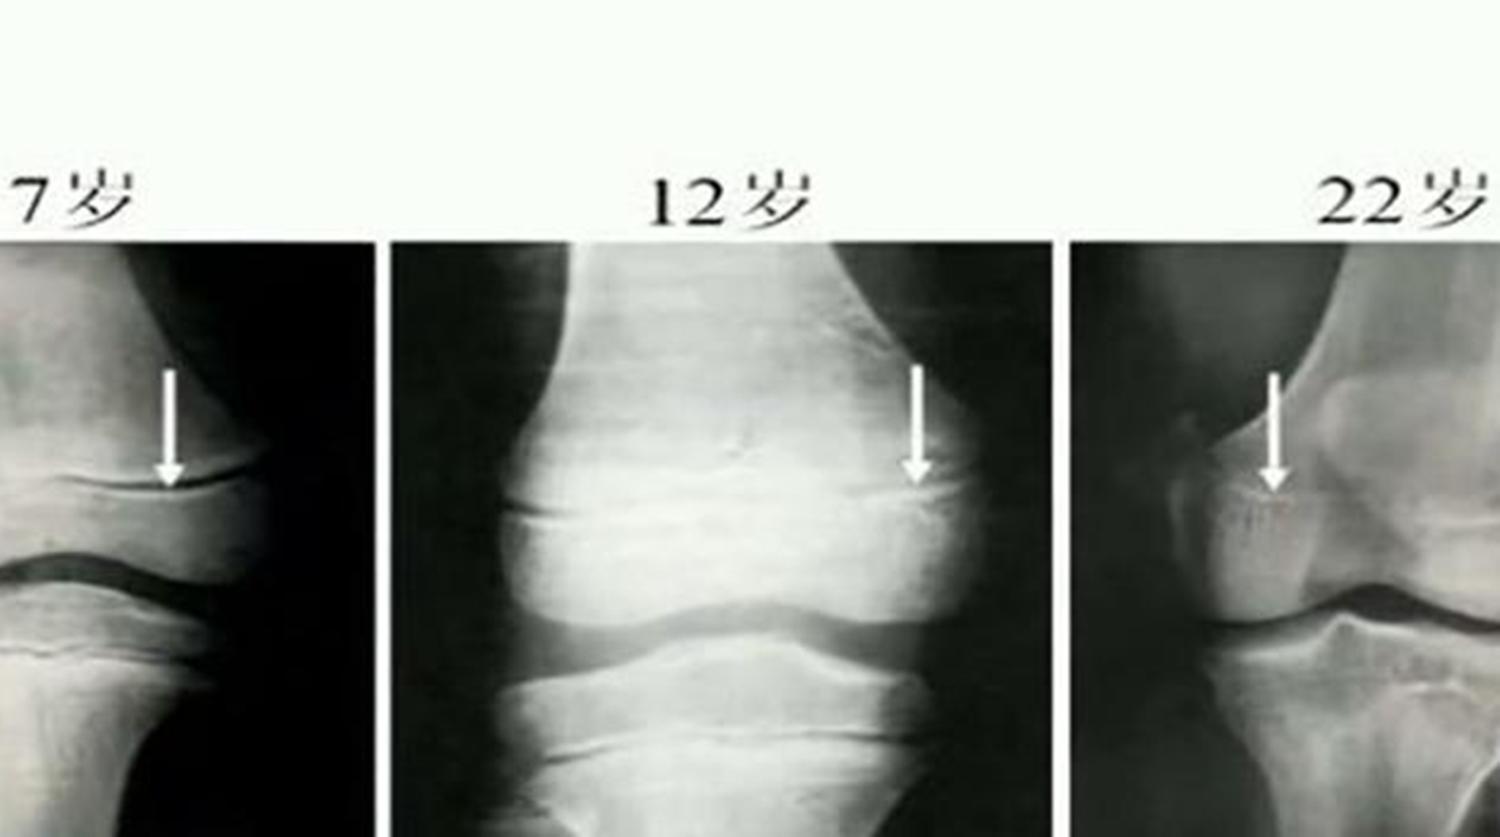

孩子骨骼成长发育,最重要的一个关键点是“骨骺线”,也就是说想让孩子长高,最关键的就是抓住孩子骨骺线闭合时间,在此之前努力。

一般情况下,男孩子的骨骺线在18岁左右的时候会完全闭合,女孩子的则会在16左右就闭合,但每个人的身体情况不一样,骨骺线闭合的具体时间也有着差异,而且也会延长。